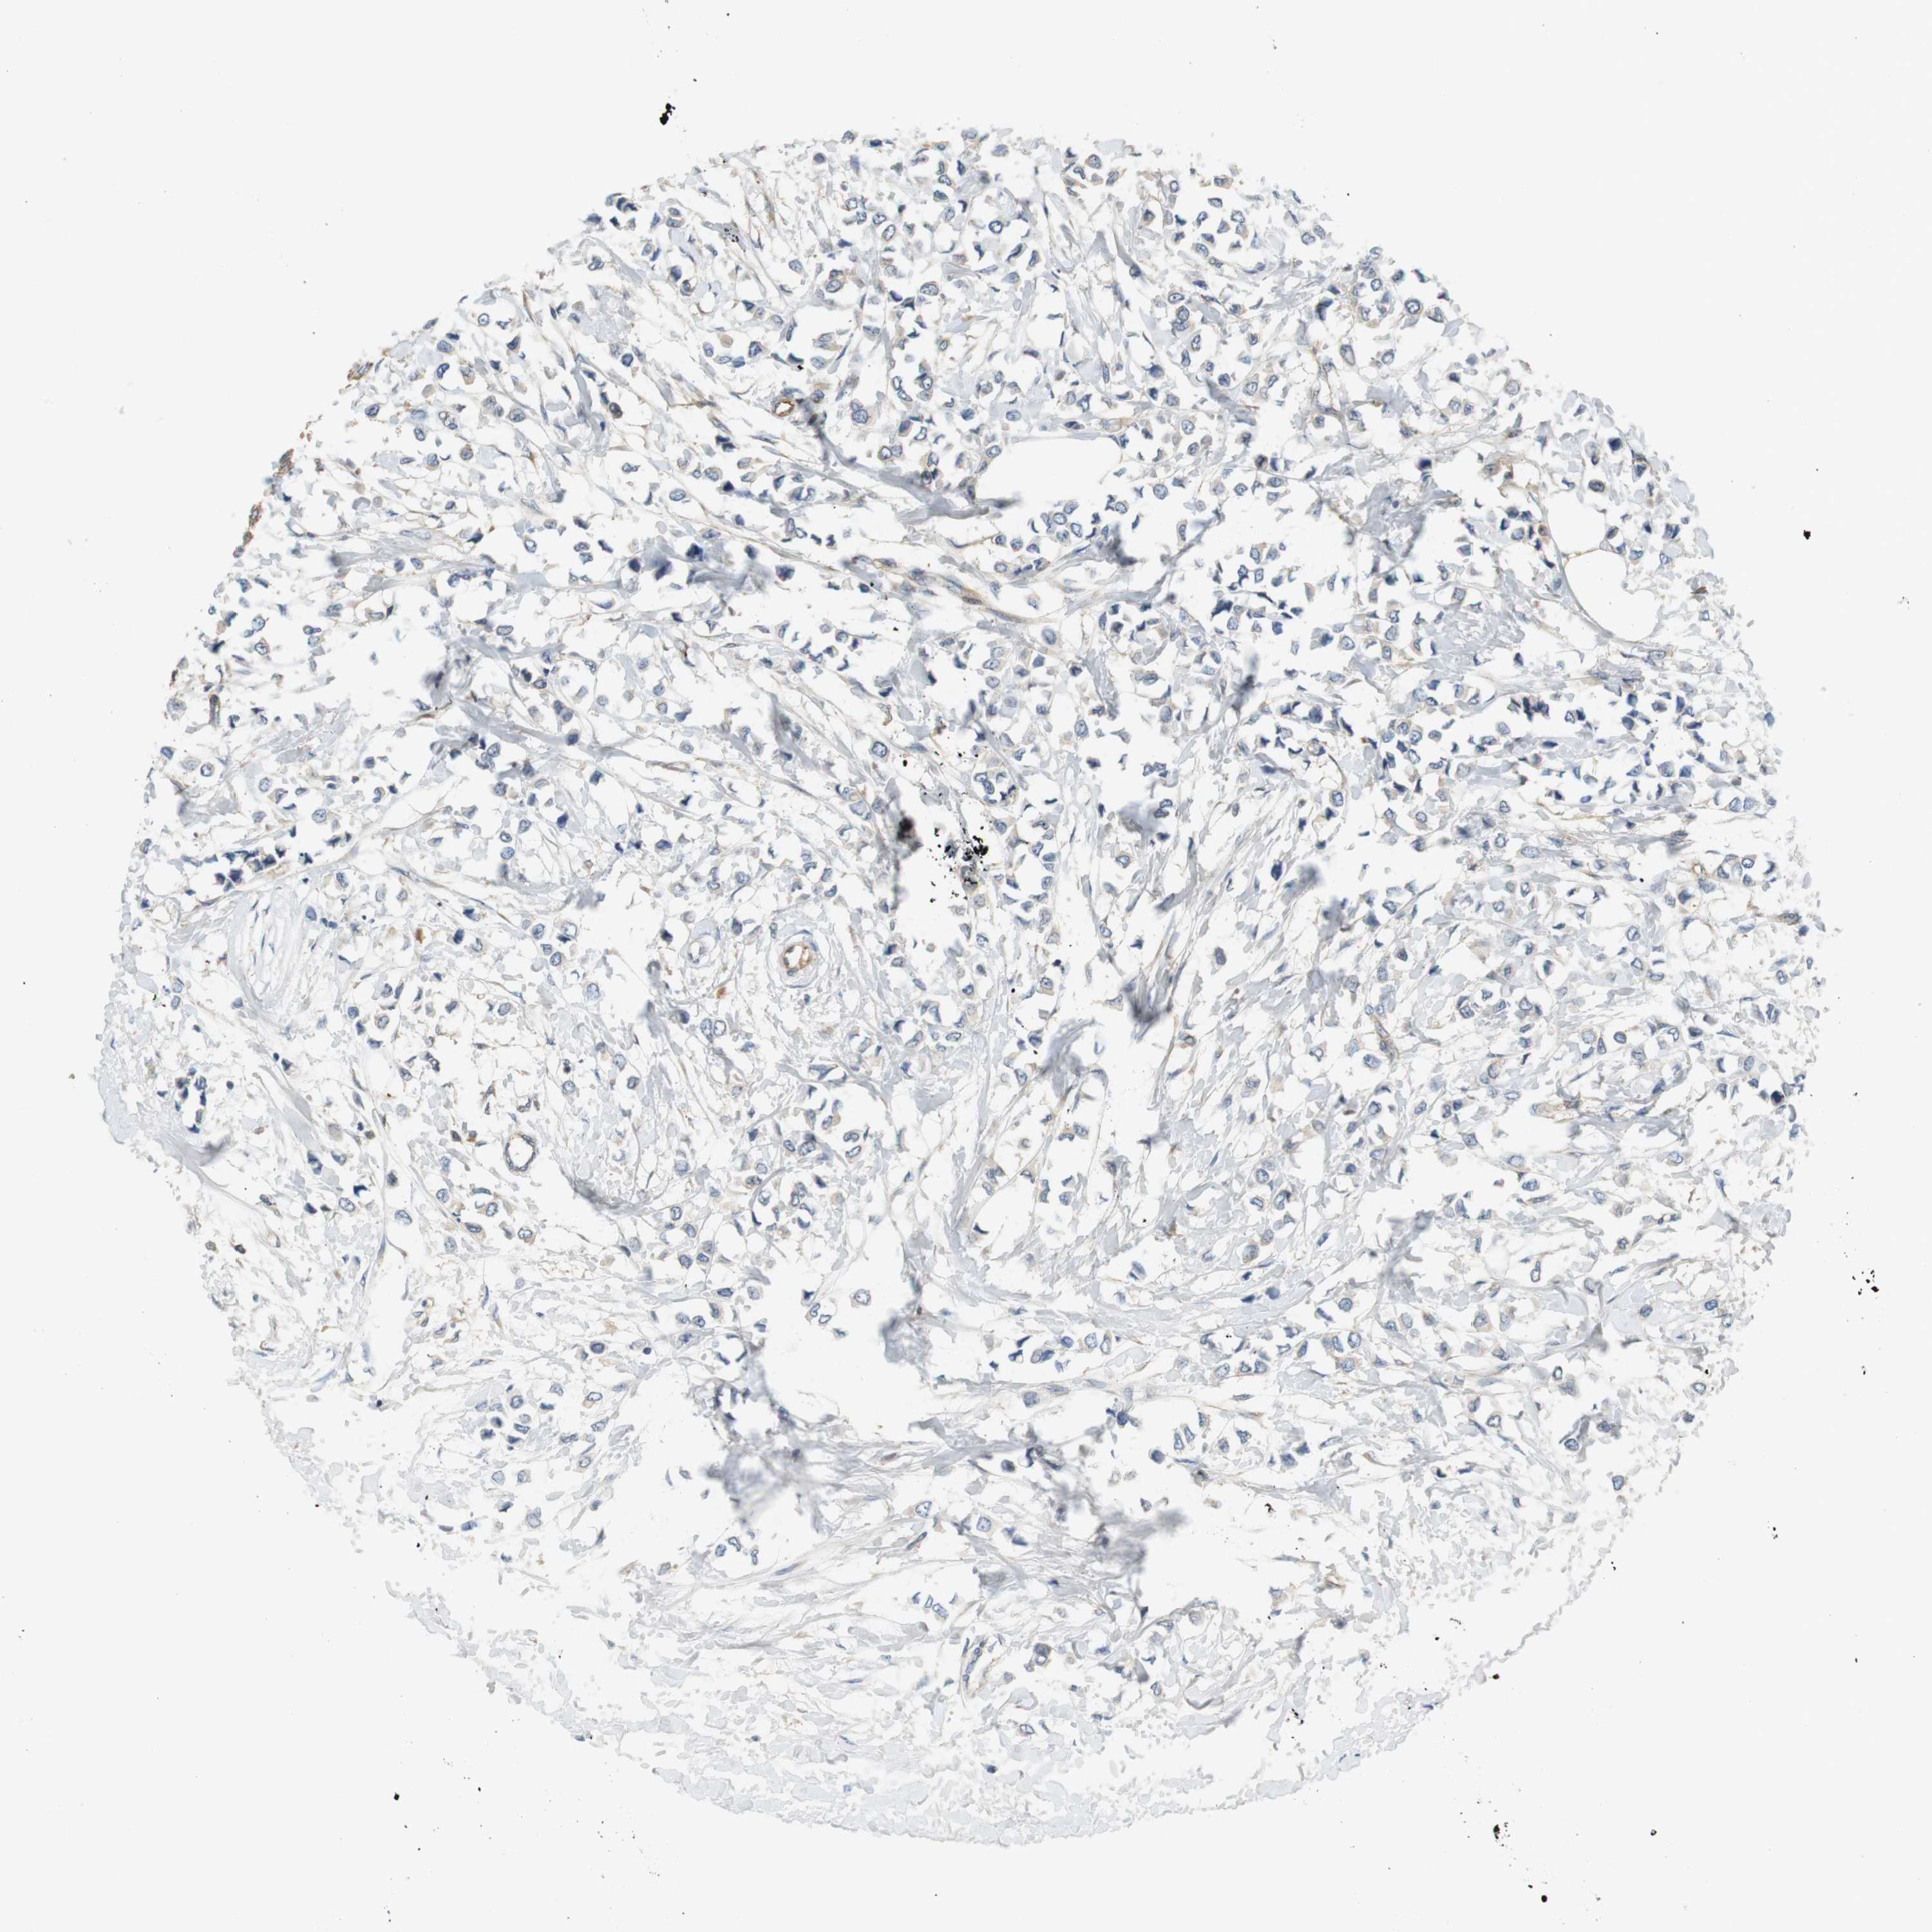

CANCER BREAST CANCER Show tissue menu

BRCA TCGA BRCA VALIDATION PROTEIN EXPRESSION

ANTIBODIES

AND

VALIDATION